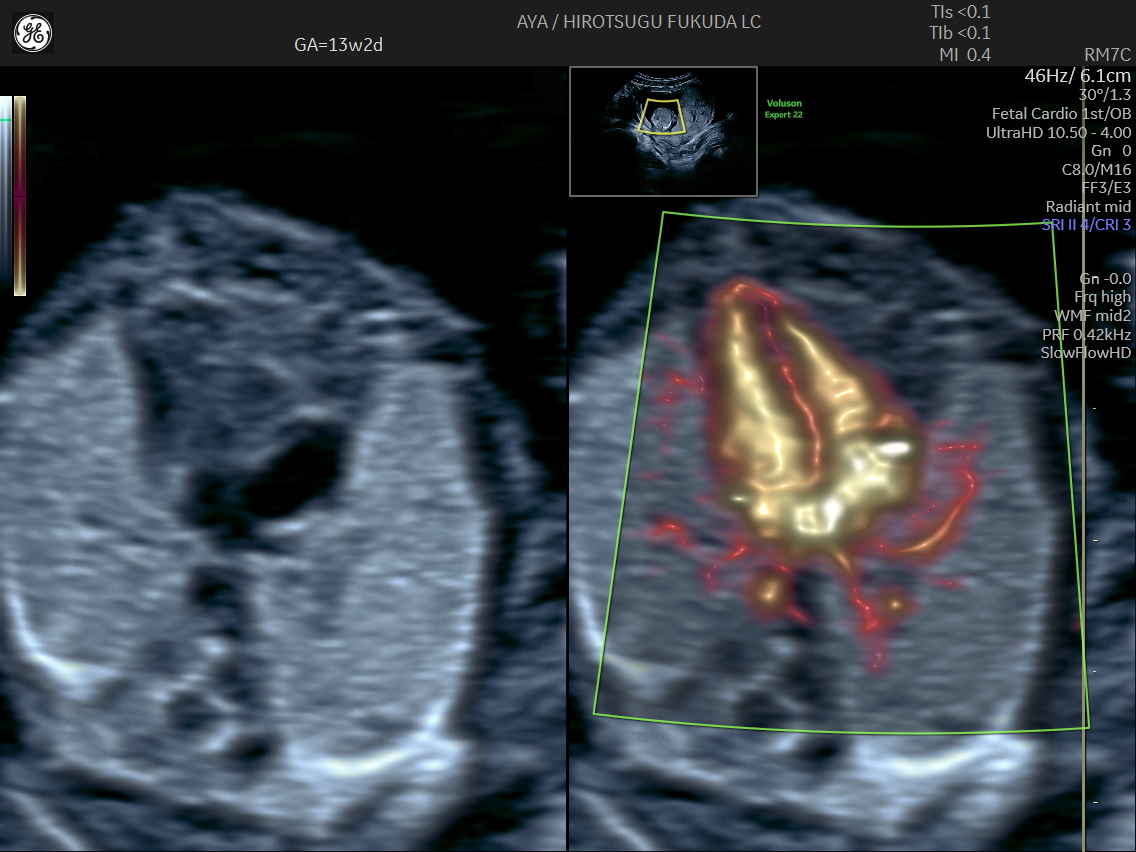

胎児心臓の初期評価

妊娠初期では観察が難しい胎児心臓についても、SlowflowHDを用いた血流描出を併用し、可能な範囲で流出路や大血管の位置関係の評価を行っています。

初期心臓評価の実際

下記は、妊娠初期における血流描出の一例です。初期心臓評価に関する取り組みについては、国際学術誌 Journal of Ultrasound in Medicine にも報告しています。

妊娠13週のslowflowHDによる心臓

妊娠13週の心疾患症例